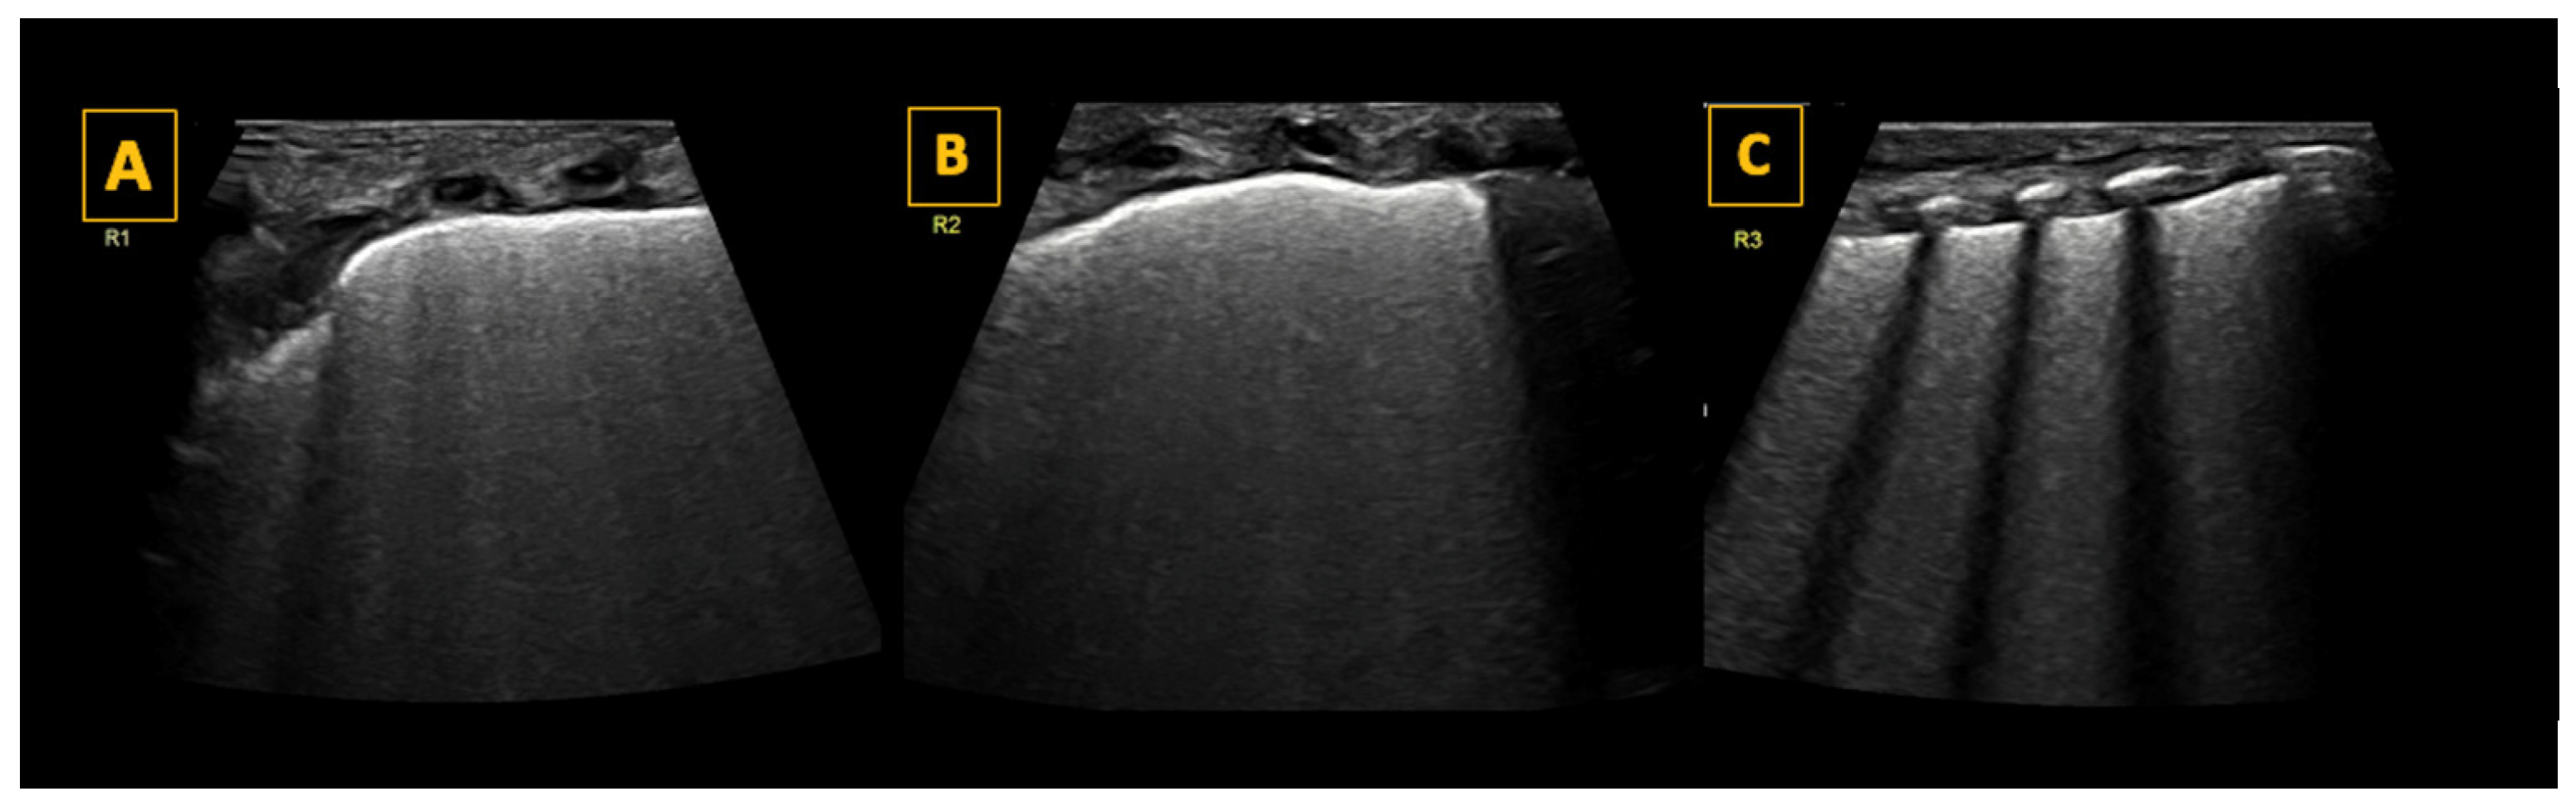

5.2. The Bat Sign

5.3. The Pleural Line, Lung Sliding, and the Lung Pulse

- The skin and underlying subcutaneous tissue.

- The thin layer of thoracic muscle.

- Ribs, which appear as oval-shaped or arch-shaped echogenic structures accompanied by anechoic vertical shadows. In the newborn, some ribs may not yet be calcified, especially in the anterior chest wall in preterm infants, and therefore no rib shadowing will be seen.

- Intercostal spaces framed by ribs and marked below by a thin, hyperechoic horizontal pleural line.